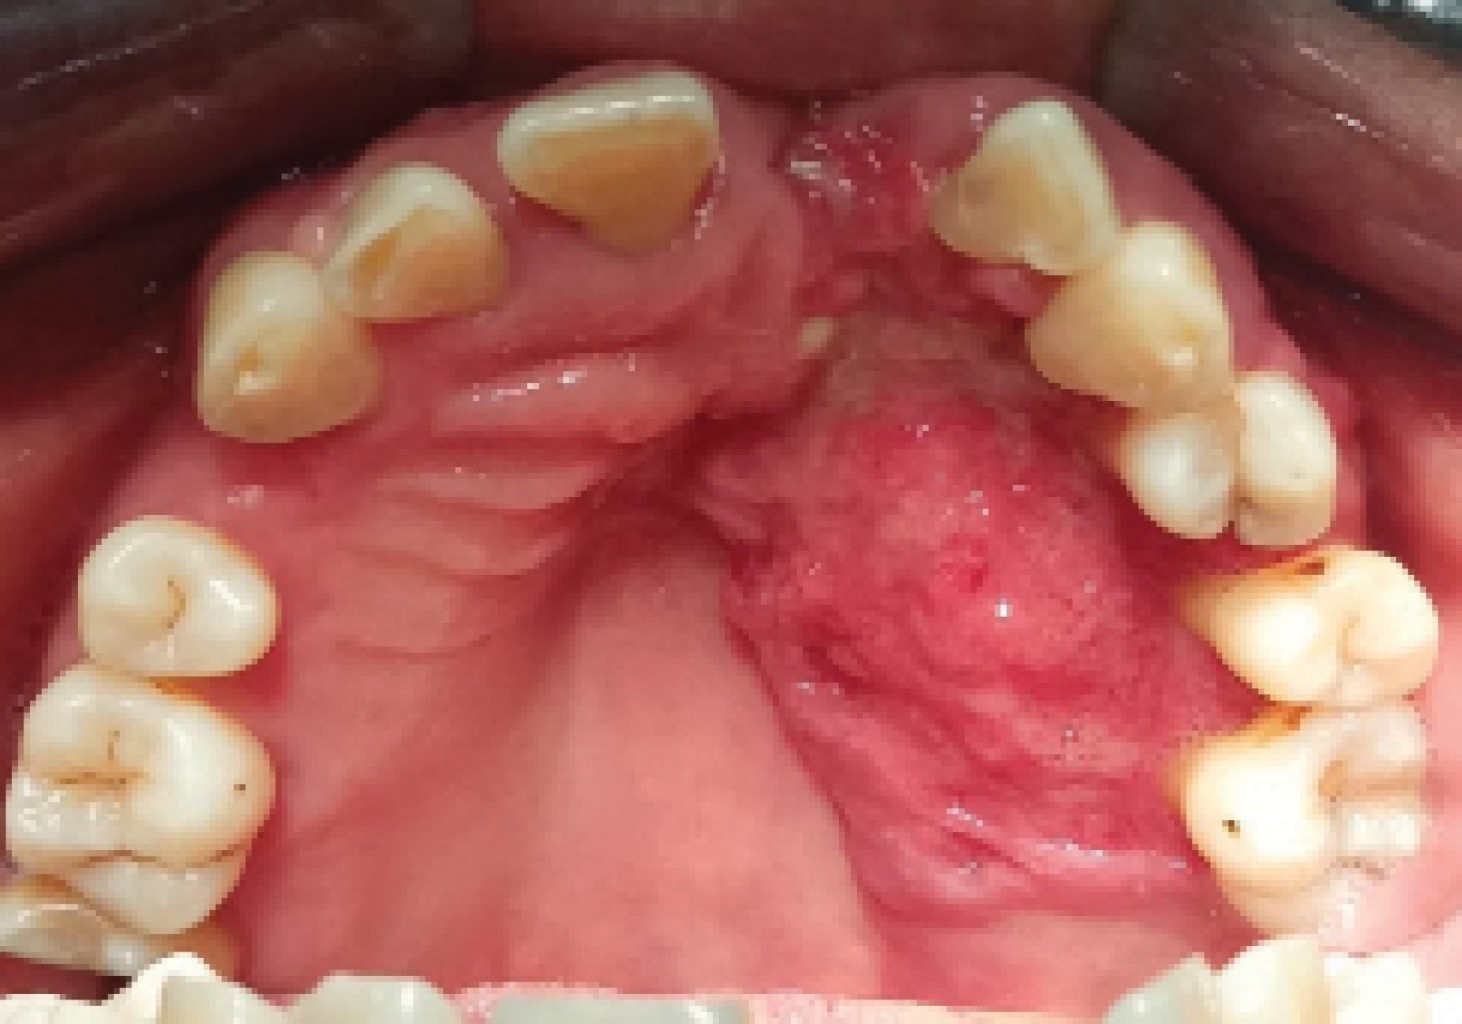

Oral squamous cell carcinoma of the palate: a case report.

Oral cancer represents a serious health problem worldwide due to its significant morbidity and mortality, it is the sixth leading cause of cancer death and has a global 5-year survival rate of 50%, largely due to the lack of recognition in early stages by patients and health professionals themselves, which causes a serious delay in diagnosis and treatment. We present the case of a 64-year-old woman with long-standing ulcers in the oral cavity who went to multiple health professionals without being diagnosed in the initial stages of the disease. She went to the Autonomous University of Tlaxcala where oral squamous cell carcinoma (OSCC) in the maxilla was diagnosed. This article emphasizes the recognition of clinical signs and precipitating factors that may generate suspicion of malignant growth and thus raise awareness among health professionals to promote prevention.

Figure 1